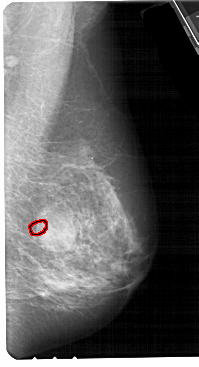

FILE: A_1705_1.RIGHT_MLO.OVERLAY

TOTAL_ABNORMALITIES 1

ABNORMALITY 1

LESION_TYPE CALCIFICATION TYPE PLEOMORPHIC DISTRIBUTION CLUSTERED

ASSESSMENT 4

SUBTLETY 2

PATHOLOGY BENIGN

TOTAL_OUTLINES 1

BOUNDARY